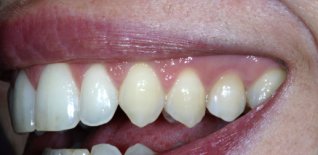

Impianto singolo a carico immediato

Dopo l'estrazione viene eseguito l'impianto e l'elemento dentario immediato.